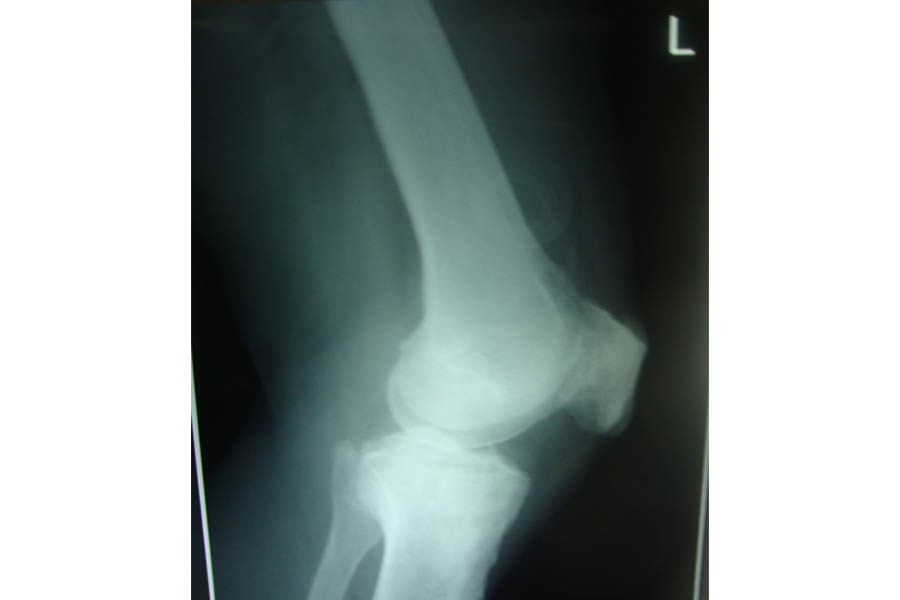

Trauma

Case 2